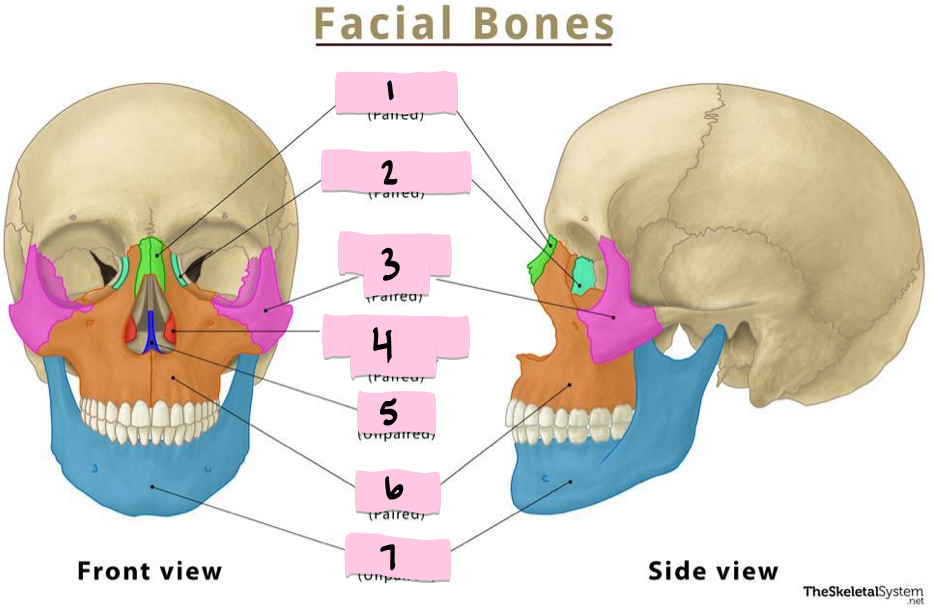

What is 1 pointing to?

Nasal bone

What is 2 pointing to?

Lacrimal bone

What is 3 pointing to?

Zygomatic bone

What is 4 pointing to?

Inferior nasal conchae

What is 5 pointing to?

Vomer

What is 6 pointing to?

Maxilla

What is 7 pointing to?

Mandible